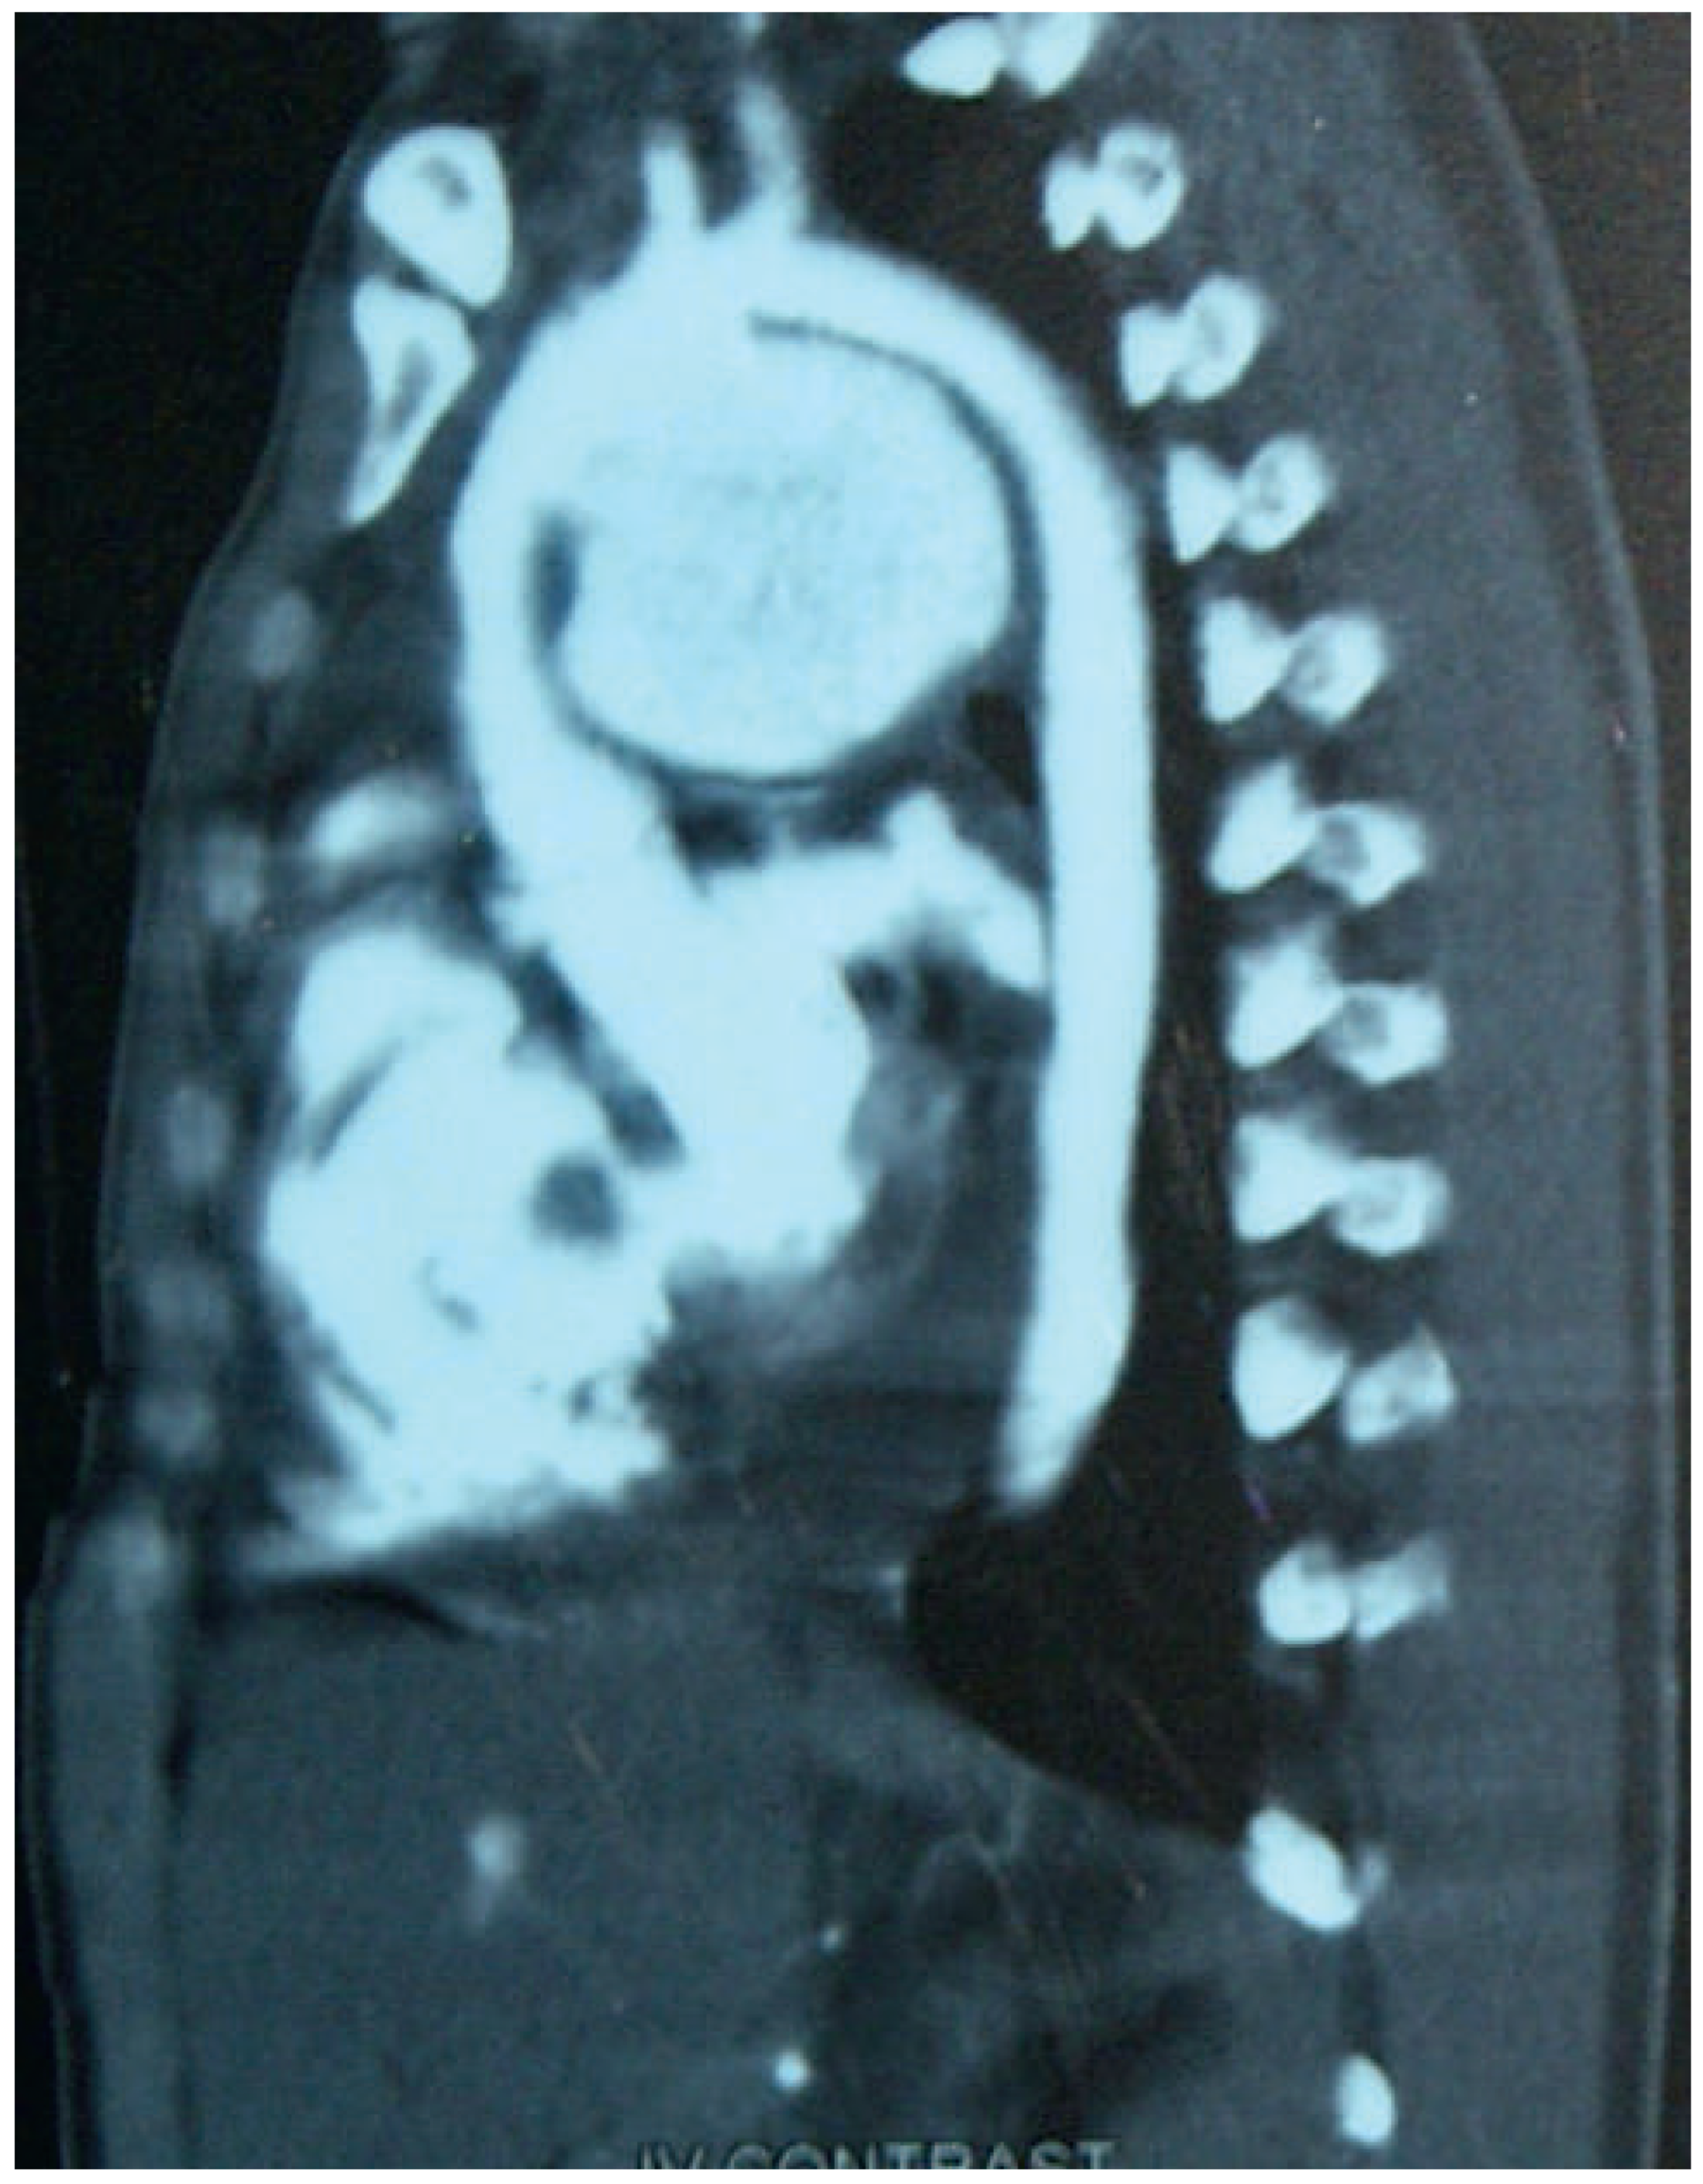

Sixteen days later, the patient complained of worsening of respiratory distress and a complete lack of exercise capacity. The chest X-ray now demonstrated marked enlargement of the heart (Figure 2). The computed tomography (CT) scan revealed a huge false aneurysm originating from the distal ascending aorta and the proximal aortic arch (Figure 3).

Figure 3. Computes tomography scan 25 days after admission: huge false aneurysm of the ascending aorta.